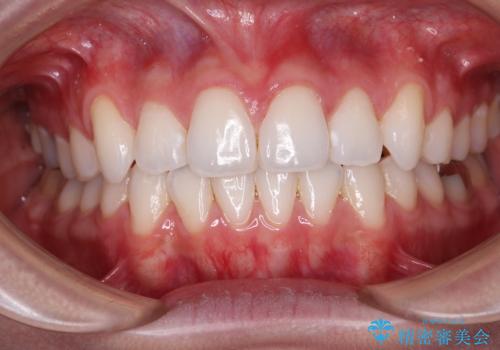

- 上顎前歯の隙間を気にして来院された患者様です。

目立たない装置を希望とのことで、インビザラインを用いて矯正治療を行うこととしました。

一度インビザラインのマウスピースセットをお渡しすると1年以上来院されず、マウスピースを破損したり紛失したりすると来院されるというのんびりとしたペースで治療を行ったため、4年間という長期にわたる治療となりました。

最終的には隙間は全て閉じ、綺麗な仕上がりとなりました。